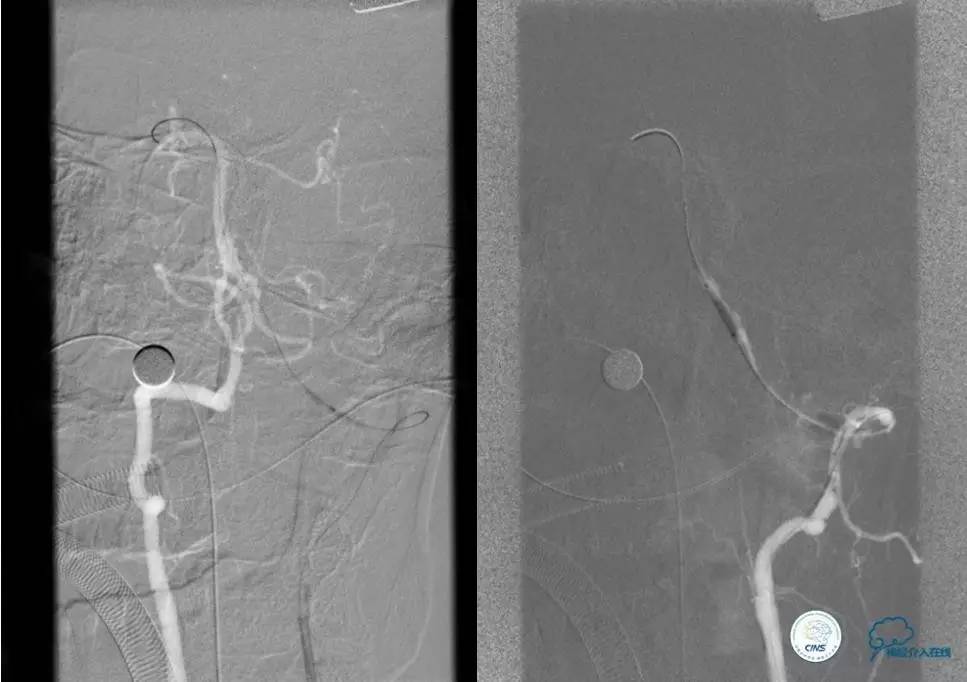

1.微导丝探查、穿过闭塞段(轻柔!)

2.微导管过闭塞段后必须造影确认在血管真腔

3.交换微导丝,撤出微导管

4.球囊预扩(原则:缓慢充盈,从小到大)

5.支架成形(保证系统稳定)

注:释放支架前及术后3天严格控制收缩压<120mmHg